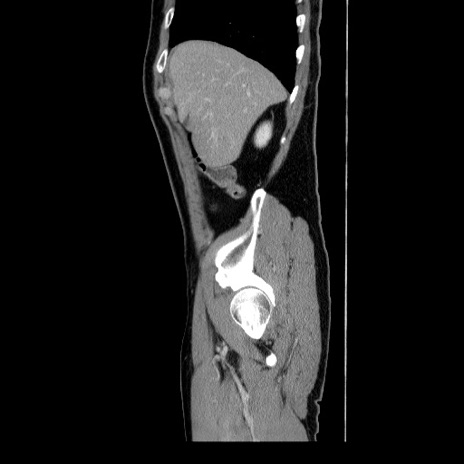

冠状断像

【症例】60歳代 男性

【主訴】右鼠径部膨隆

【現病歴】1年程前より右鼠径部膨隆あり。自己にて還納可能だったため放置していた。3時間前より右鼠径部の脱出を認め、還納困難となり受診。

【身体所見】右鼠径部に小児頭大の膨隆あり。弾性硬であり、用手還納は困難。左鼠径部にも膨隆を認める。脱出はなし。